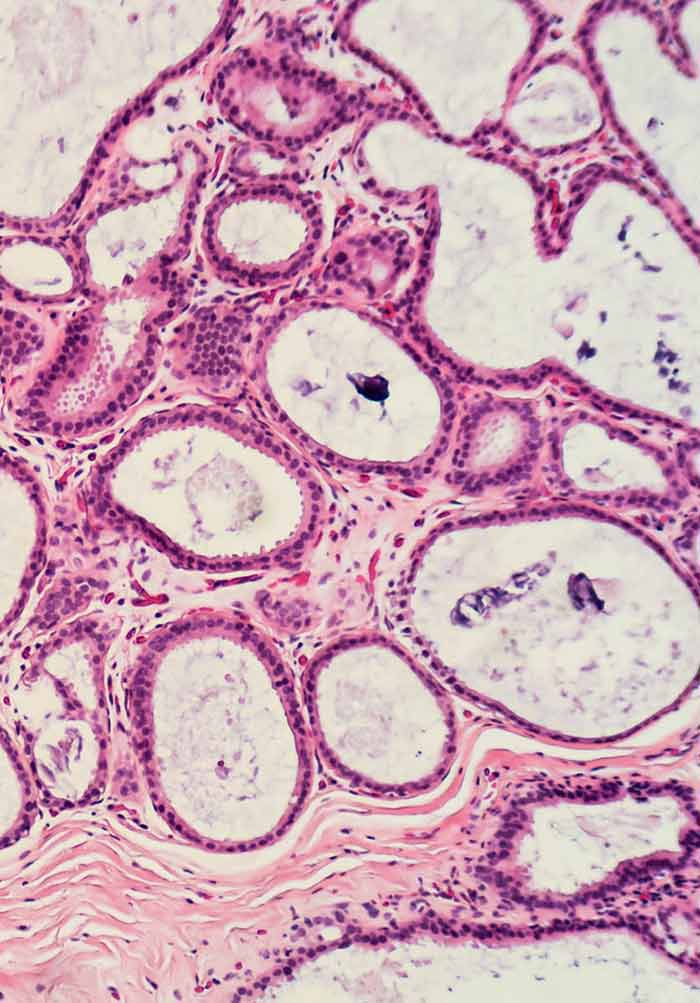

Dysplasia

Oral Cancer And Potentially Malignant Disorders Intechopen

Oral Cancer And Precancerous Lesions Neville 2002 Ca

Carcinoma In Situ Of Oral Cavity Dermnet Nz

Oral Cancer And Precancerous Lesions Neville 2002 Ca